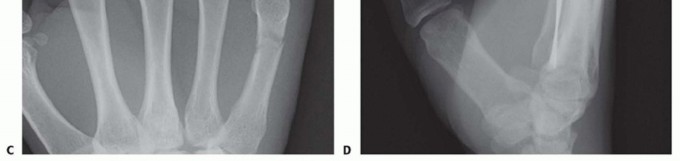

Standard radiographic imaging forms the cornerstone of diagnostic evaluation, requiring, at minimum, a dedicated posteroanterior (PA), a true lateral, and a pronated oblique view of the injured hand. The PA view is excellent for assessing coronal plane angulation and transverse displacement, though it notoriously underestimates sagittal plane deformity. The true lateral view is critical for quantifying apex-dorsal angulation, though overlapping metacarpal shadows can complicate interpretation. The pronated oblique view often provides the clearest visualization of the fracture profile and the degree of comminution.

When standard radiographs are equivocal, or when dealing with complex intra-articular fractures and suspected CMC fracture-dislocations, advanced cross-sectional imaging is mandatory. High-resolution Computed Tomography (CT) with 3D reconstructions provides unparalleled detail of articular step-offs, occult comminution, and the precise spatial orientation of fracture fragments. This information is invaluable for determining the feasibility of lag screw fixation versus the necessity of bridge plating. Furthermore, obtaining radiographs of the uninjured, contralateral hand serves as a vital anatomical template, allowing the surgeon to accurately gauge the patient's native metacarpal length and intrinsic diaphyseal curvature.

Clinical & Radiographic Imaging Archive